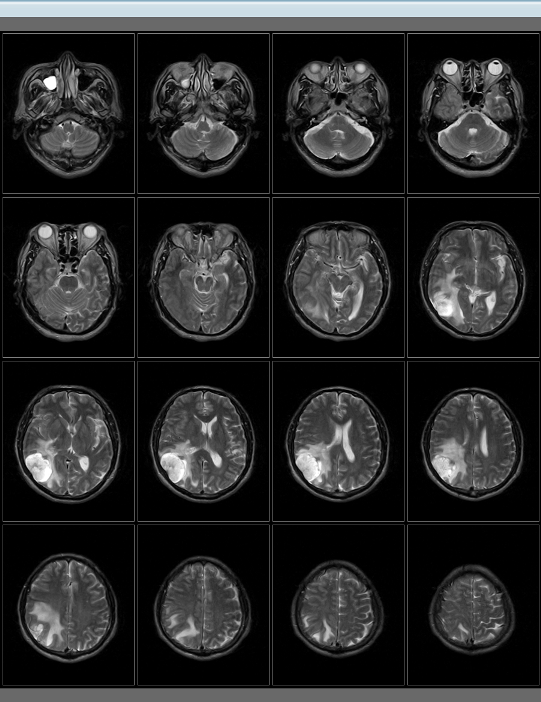

Neuro Imaging

La Neuro suite fornisce protocolli di scansione ottimizzati con alta risoluzione, alta qualità d’immagine ed elevato rapporto segnale rumore per facilitare la diagnosi.

L’esame MRI di 20 minuti della scansione cerebrale del PICA è un esempio del nostro impegno nel fornire valore, prestazioni e innovazione.